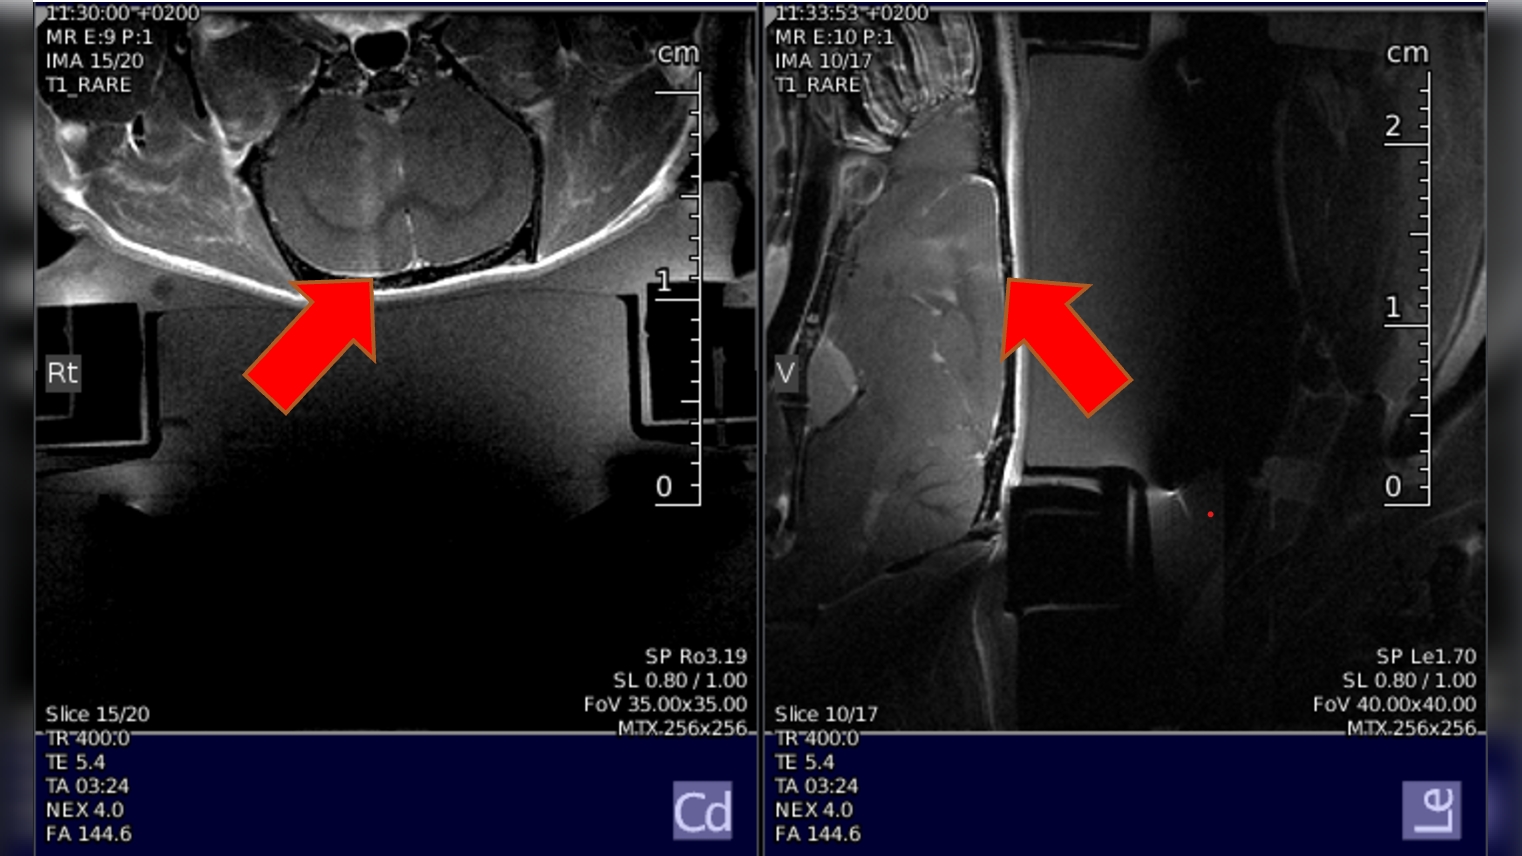

Read more →FUS with preclinical MRI allows brain drug delivery via BBB opening, localized heating, and MRI thermal mapping

Read more →MR measurements of nonliving samples, MR measurements in vivo (mice, rats)